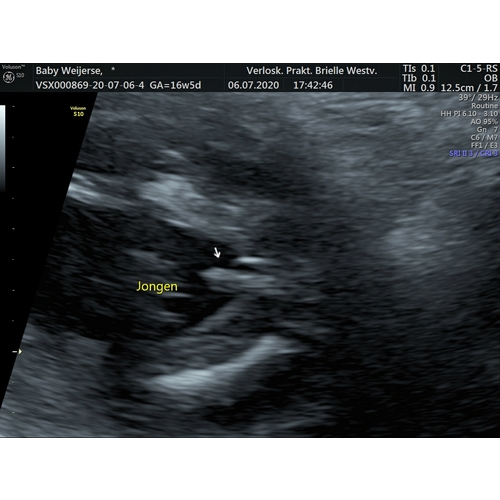

Bij jou zie je duidelijk 2 beentjes uit elkaar en het piemeltje dat naar links wijst en de balletjes ertussen 😍 gefeliciteerd!